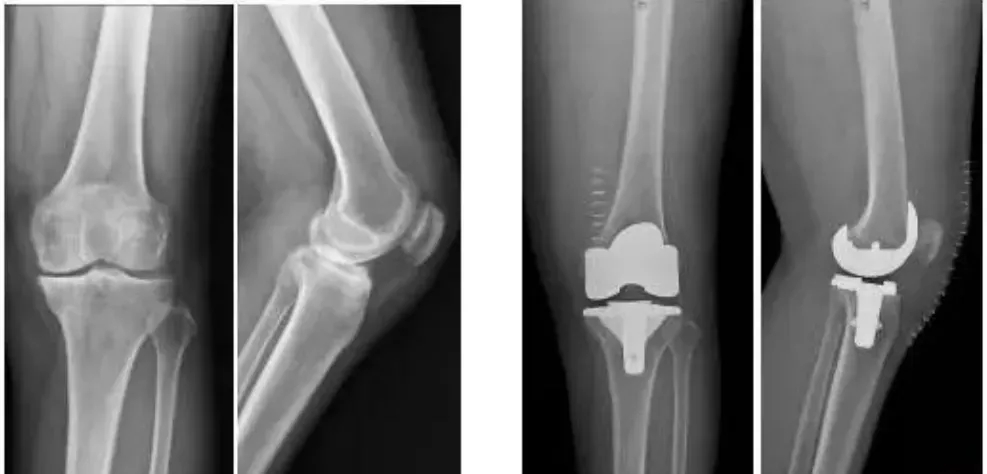

全球首款3D打印分區骨小梁生物型膝關節假體

這種新型假體與傳統骨水泥假體相比,其通過假體—骨界面緊密接觸,促使骨組織長入假體,提高假體與髓腔的結合強度,從而達到假體的長期穩定。使用生物型人工膝關節,可保存患者骨量,同時避免或降低了骨水泥所導致的毒副作用。

本次植入的生物型膝關節假體在術中無需使用骨水泥,通過機械方式進行固定,即假體與骨組織的緊密結合,獲得假體的初始穩定性,遠期骨組織長入假體表面的微孔內部,實現由機械固定向生物內鎖固定的轉化,終經過骨整合作用獲得良好固定,預期能夠獲得更長的假體壽命。

周宗科教授介紹說,該款3D打印分區骨小梁生物型膝關節假體有三個亮點,一是脛骨平臺假體采用了3D打印骨小梁分區技術,三分區設計使宿主骨均勻骨長入,避免因應力分布不均而造成平臺假體松動等問題;二是所用股骨髁假體表面為真空等離子噴涂純鈦涂層,其粗糙的接觸面增加了骨誘導的能力,具有優異的即刻穩定和長期穩定性;三是所用平臺墊為添加維生素E的高交聯超高分子量聚乙烯材質,具有優異的耐磨性能。